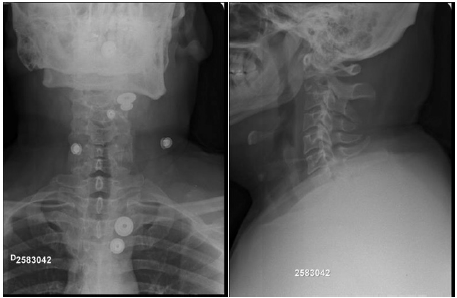

According to the patient’s symptoms and physical examination, X-ray photographs of the cervical and thoracic spine were requested, providing altered findings. Multilocular, radiolucent, cystic mass level CII/CIII was visualized, surrounded by septation of bone tissue with diverticular-shapedinternal projection son the cyst wall, besides the cortical discontinuity of the CII vertebral body.

Five years after the surgical interventions, the patient keeps the same job with cross bite complaint and periodontal pain. Panoramic X-ray photographs were taken, the image suggesting generalized horizontal bone loss, yet without alterations in the plate and screws positioning in CII/CIII. Therefore, the patient has under gone dental follow-up (Figure 1-6).

Figure 1: Bone cystin RX.

Figure 6: Final RX.

Aneurysmal bone cysts of the spine are rare, presenting predilection for the lumbar spine [34-38] and raising great consideration regarding differential diagnoses. They are: osteoblastomas, osteosarcomas, osteoid osteomas, giant cell tumors, aneurysmal bone cyst, osteochondromas, chondrosarcomas, chondromas and Ewing sarcoma [24]. Gidding et al. point out the history of sub periosteal trauma with an incorrect and exaggerated repair, with the presence of hemorrhage [34,39]. In the case described herein, the patient did not report any remote traumas in his vertebral spine. We thus resorted to the hypotheses of primary tumor of genetic or even vascular etiology. We here present the case of an adult male with CII aneurysmal bone cyst, who checked in our service with a complaint of mechanical neck pain, hypersensitivity, besides limited cervical motion. X-ray photograph, despite being an in conclusive imaging exam for aneurysmal bone cysts [40], was requested, with typical findings, such as rare faction are as, well circumscribed lytic lesion, and the presence of thin trabeculae.Some authors consider pre-surgery puncture biopsy dispensable, having image tests as the only basis. In this case, pre-surgery puncture biopsy in CII was performed, which allowed discarding other pathologies, making the diagnosis of aneurysmal bone cyst conclusive. Treating aneurysmal bone cyst is challenging, and in the literature researched, although selective arterial embolization (SAE) is described as a first-choice treatment, there was a great trend for surgical treatment with complete resection of the lesion due to the success verified in multiple cases described. A number of authors consider curettage alone a high risk for relapses, considering the adjuvancy with Phenol or Ethanol [40-42]. In this case report, due to the locally aggressive behavior of the tumor, cervical spine instability, expansibility and neurological complications, we opted for surgical resection, grafting, stabilization and local infusion of corticoid. Similar cases are described in the literature journals, also at three surgical times, yet we identified changes in the order of the approaches. Other authors considered performing the biopsy followed by resection and cervical spine stabilization, whereas in our case, stabilization was performed at the second time with cervical arthrodesis of CI/CII and grafting. The resection of vertebral discs CII/CIII and of the Odontoid body was performed at a third time, with the association of plates and screws, after the patient’s signs of myelopathy. The control of the patient through CT was performed eight months after the last surgical intervention, with successful system stabilization. The objective was thus met, with the complete excision of the tumor, reduced risk of relapse and minimum morbidity.